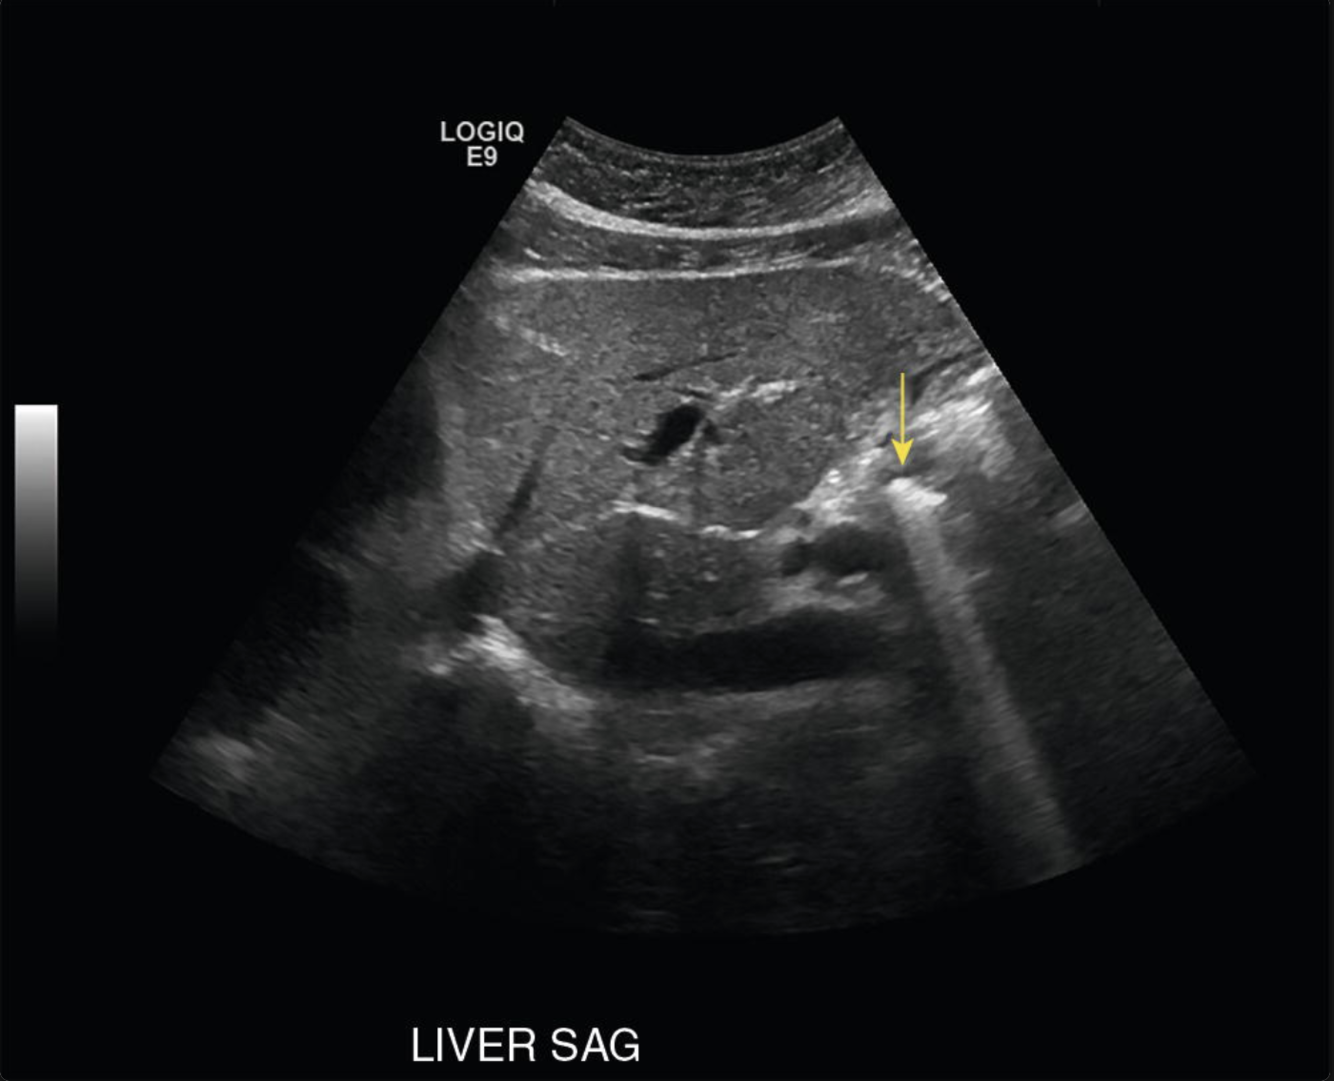

Which phenomenon is responsible for the following US artifact?